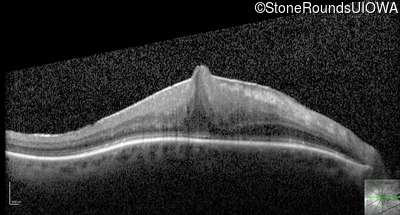

Optical Coherence Tomography - Right - 20/200 sc

Exemplar / OCT Stack

OCT Stack